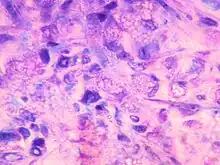

Coupe histologique de muscle de souris injecté avec une solution contenant des particules d'hydroxylapatite